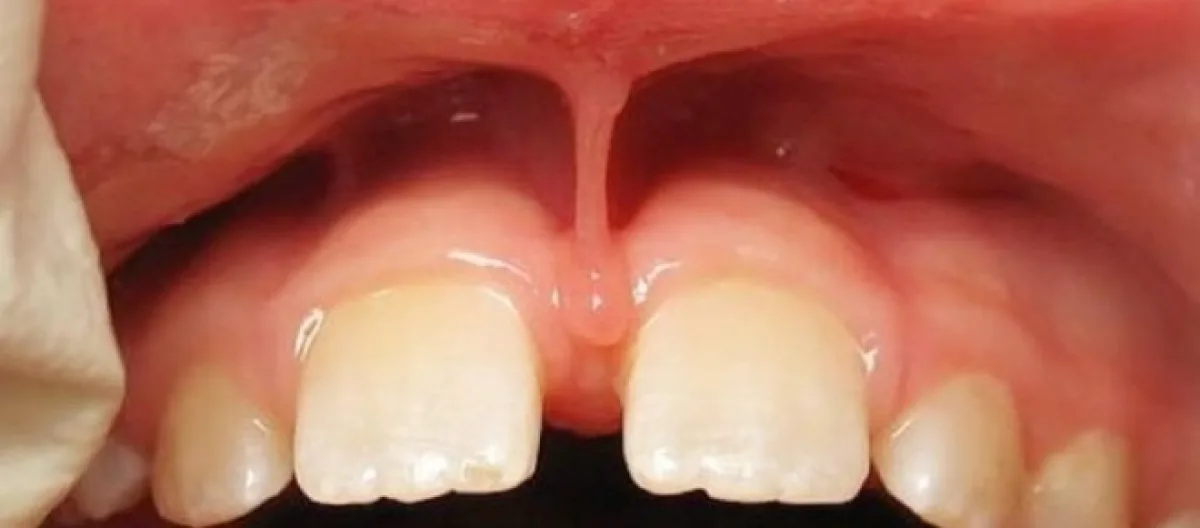

Freios labiais são pregas da mucosa inseridas de um lado na parte interna do lábio e do outro na gengiva. São também denominados frênulos e são três: superior, inferior e lingual. A inserção dos freios labiais seguem a seguinte classificação:

A depender do local de sua inserção ele pode causar limitações nos movimentos da língua e dos lábios, problemas estéticos, dificultar o fechamento de diastemas, dentre outros.

A indicação mais frequente de frenectomia ocorre por indicação do ortodontista quando há dificuldade de fechamento de diastemas (espaço entre os dentes - neste caso os dois da frente) devido à posição do freio labial entre eles. Outra indicação neste mesmo tipo de caso é realizada pelo Odontopediatra quando ocorre dificuldade de higienização dos dentinhos pelos pais.